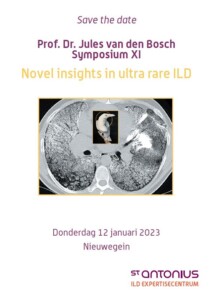

Save the date voor alweer het 11e prof. dr. Jules van den Bosch Symposium.

We hopen dat het dit jaar fysiek door kan gaan in het auditorium van ons ziekenhuis in Nieuwegein.

Accreditatie NVALT zal worden aangevraagd.

Het volledige programma volgt zo spoedig mogelijk.

Aanmelden kan natuurlijk al: graag via m.kingma@antoniusziekenhuis.nl met vermelding van uw BIG-nummer.